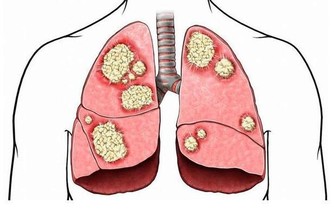

作為人體的排毒器官,肝臟負責將人體的有毒物質分解轉化,

當毒素多到肝臟無法分解的時候,就會留在肝臟中,

肝臟中堆積太多的有毒物質勢必會傷害肝細胞,時間久了,肝細胞就會死亡。